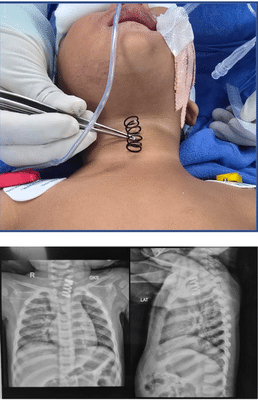

- AIIMS doctors remove 2-inch-long metal spring from 14-month-old's food pipe